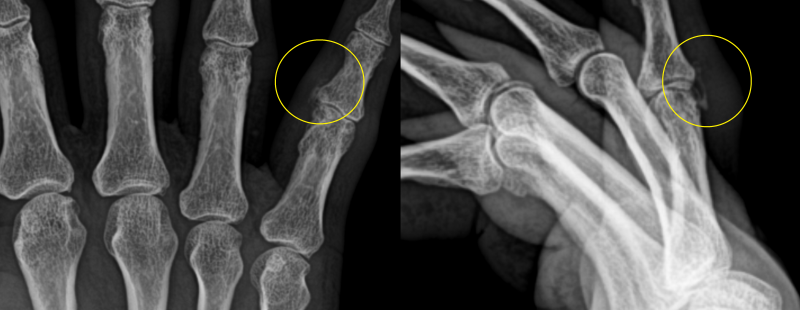

손가락 석회[석회성 건염]

먼저 오자마자 초음파를 봤어요 석회의 크기가 전과 별 차이가 없네요.다시 한번 제대로 치료를 하기로 했어요.-치료방법-1.주사요법2.충격파3.석회흡입술